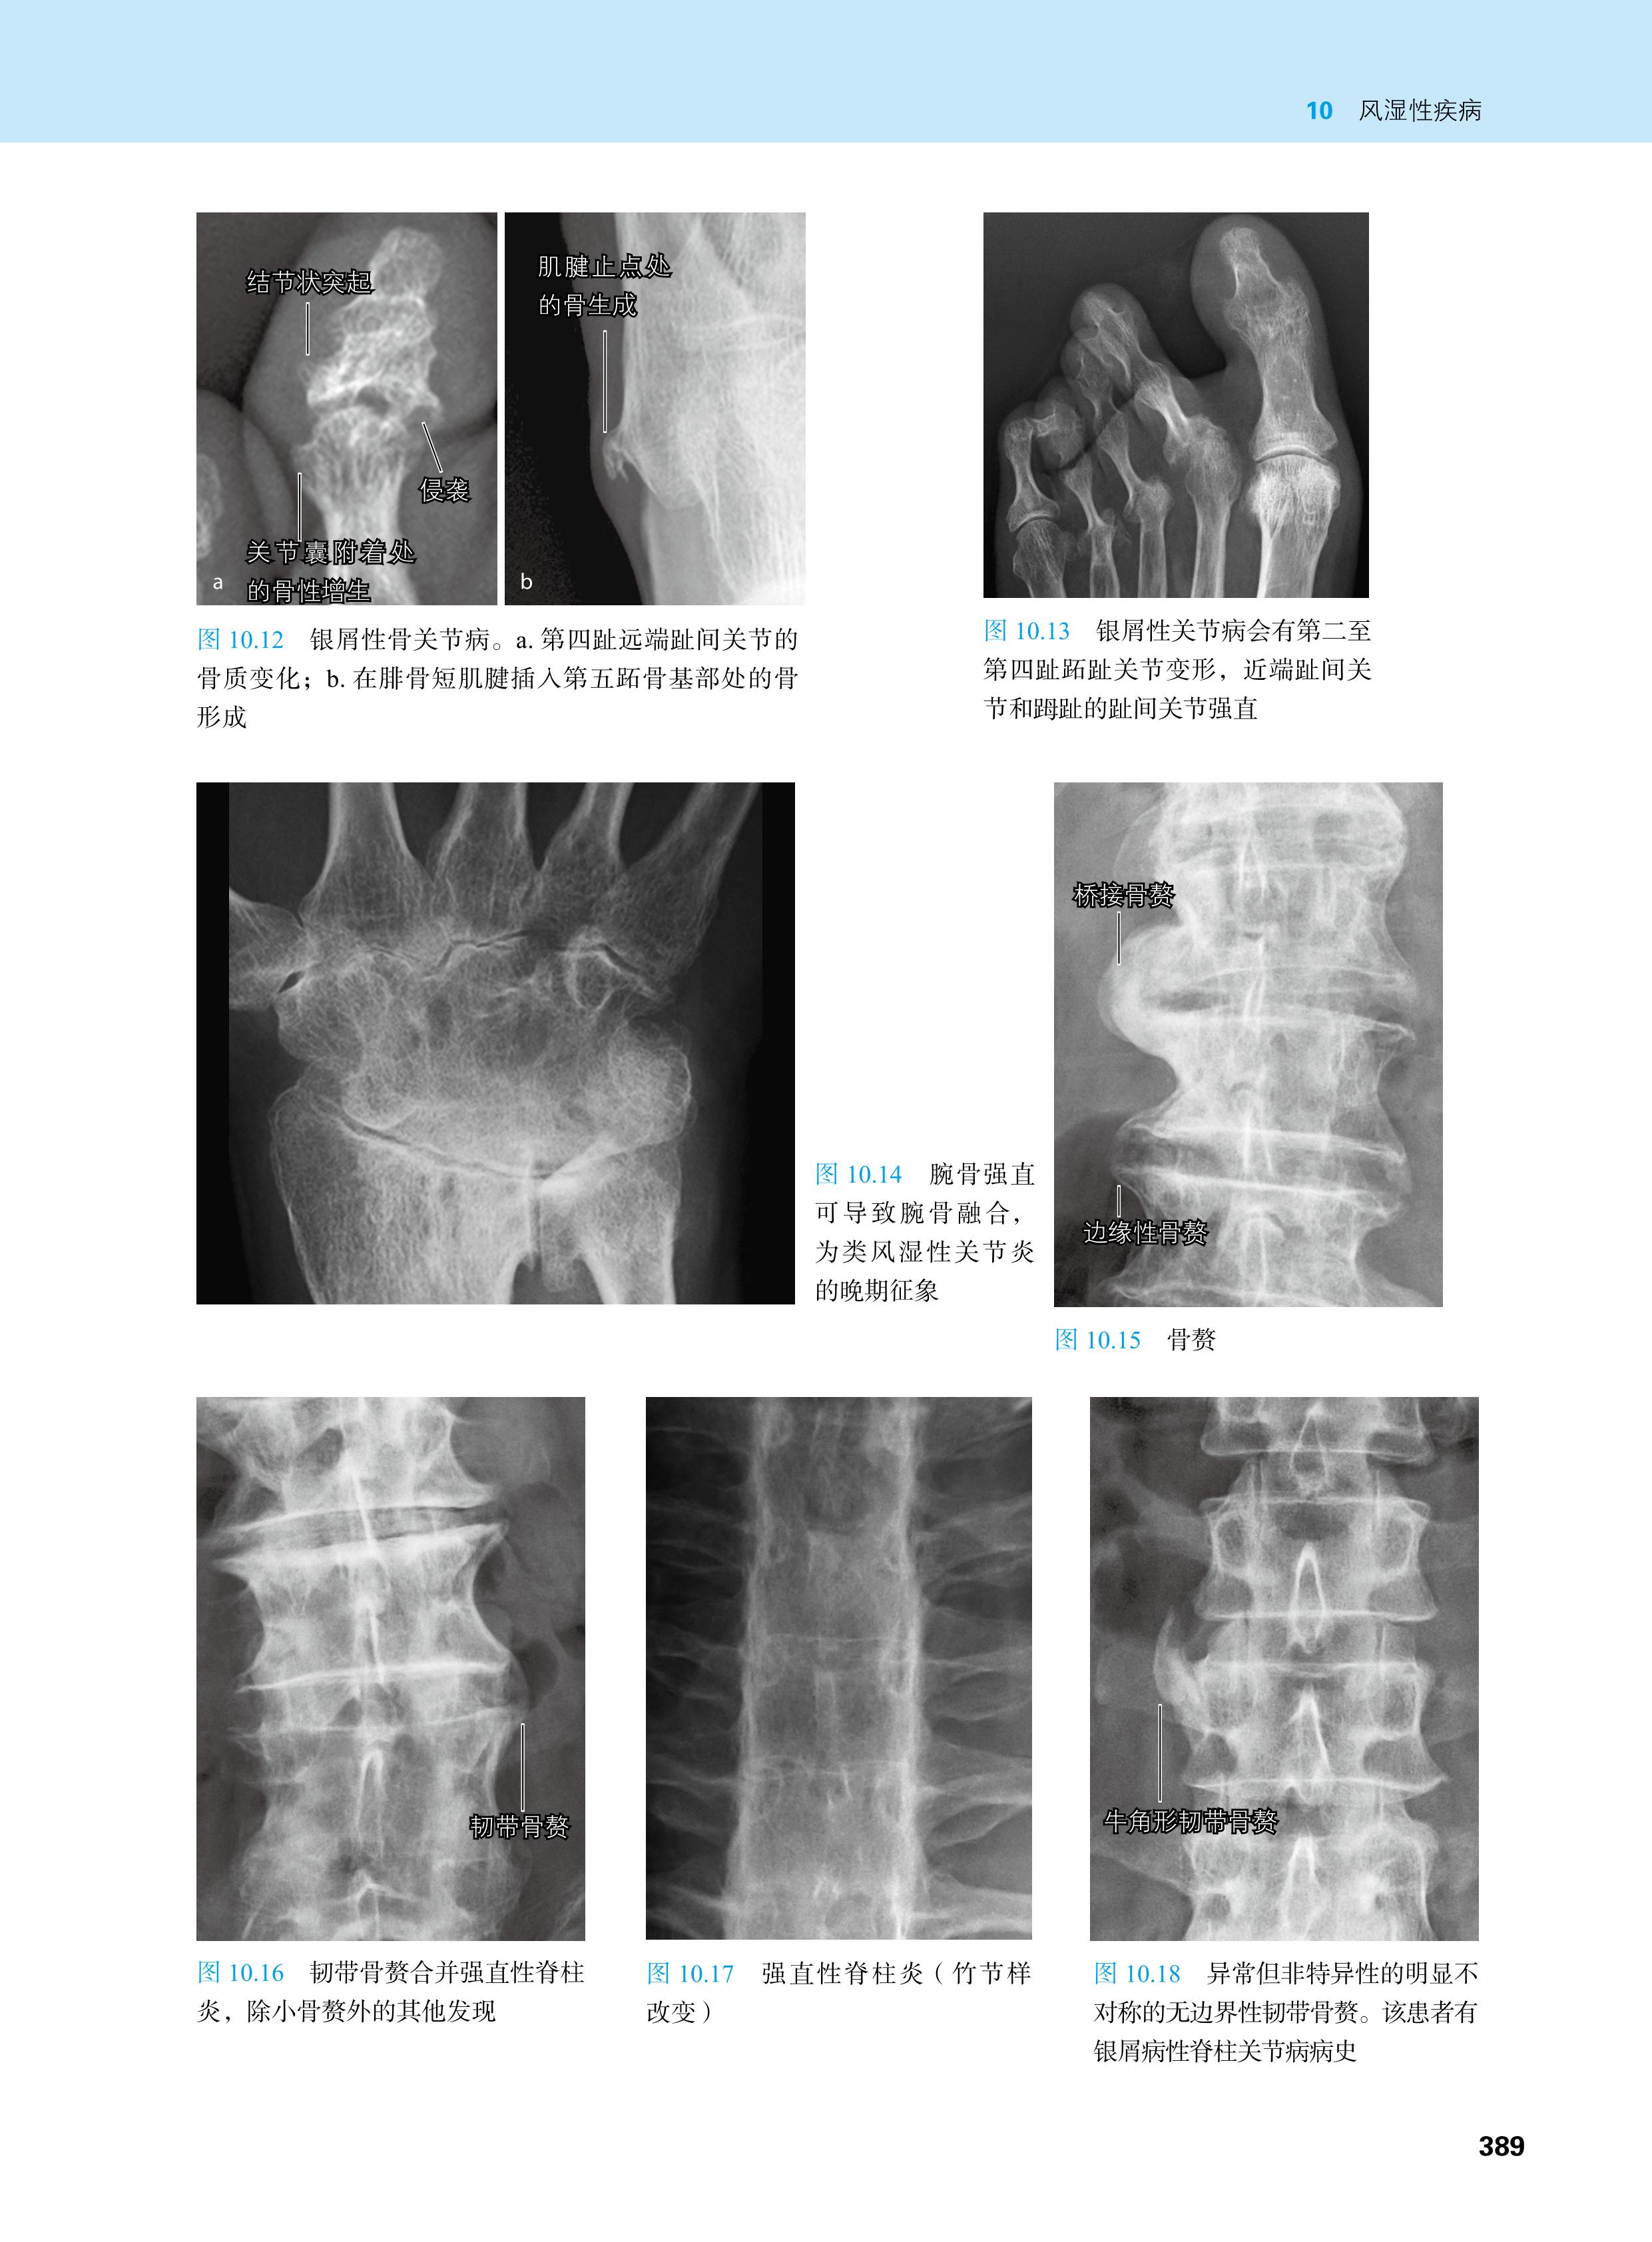

本书由来自欧美的40余位骨科、影像科专家编写而成,分12个章节,用凝练的文字,大量的影像资料片、示意图和表格,比较详细地介绍了各种骨科疾病的影像诊断、鉴别诊断、成像技术选择,以及治疗和预后等,涉及各种骨关节先天性疾病、创伤、退变、感染、肿瘤等,基本囊括临床常见骨关节疾病,方便骨科、关节外科、风湿科、影像科等专业的医师快速查阅。

·2000余幅影像资料片、示意图和大量图表,方便读者快速查阅

·内容包括各种骨关节先天性疾病、创伤、退变、感染、肿瘤等,基本囊括临床常见骨关节疾病